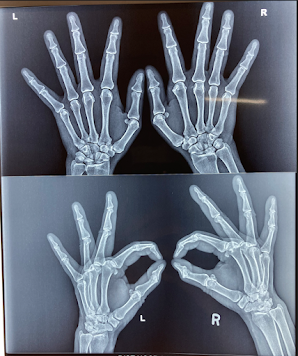

This year 2022, the World Arthritis Day Theme is “It’s in your hands, take action“, addressing the world population to join hands for this cause to make this event fruitful for those deprived of the support.

The theme “It’s in your hands, take action” aims to encourage people with arthritis, their caregivers, families, and the general public to avail every opportunity to take action to improve their lifestyle.